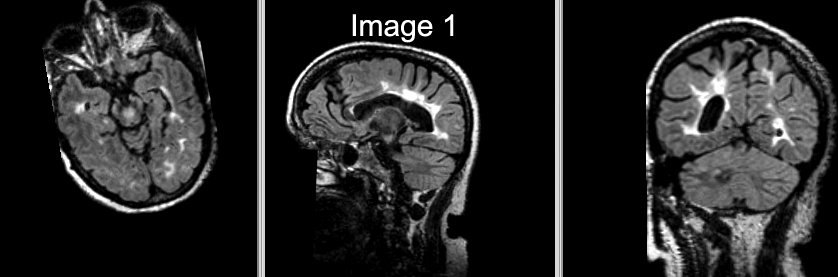

Slicer Registration Library Case #16: Manual alignment of intra-subject Brain MRI

This is a classic case of change assessment. We want to know if the tumor changed since last exam.

reference/fixed : T1 SPGR , 1x1x1 mm voxel size, sagittal, RAS orientation.

moving: T2 FLAIR 1.2x1.2x1.2 mm voxel size, sagittal, RAS orientation.